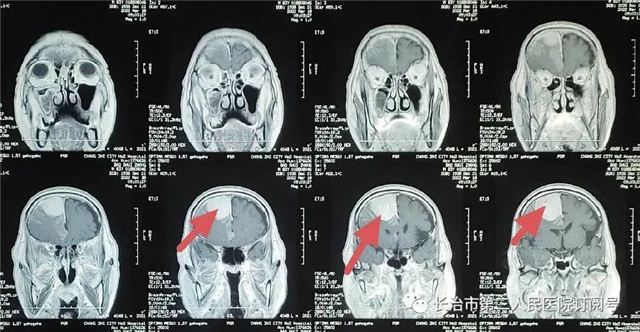

▲术前CT见:后颅窝占位

▲核磁检查见小脑幕下肿瘤,强化明显,考虑脑膜瘤。

(红色箭头为肿瘤)

▲术后复查:肿瘤全切、术野干净未见出血

本病例因幕下空间小,肿瘤压迫小脑,紧邻横窦、窦汇、脑干。手术风险高一旦出血,将危及生命。术后复查肿瘤切除干净,瘤腔未见出血。现患者已痊愈出院。